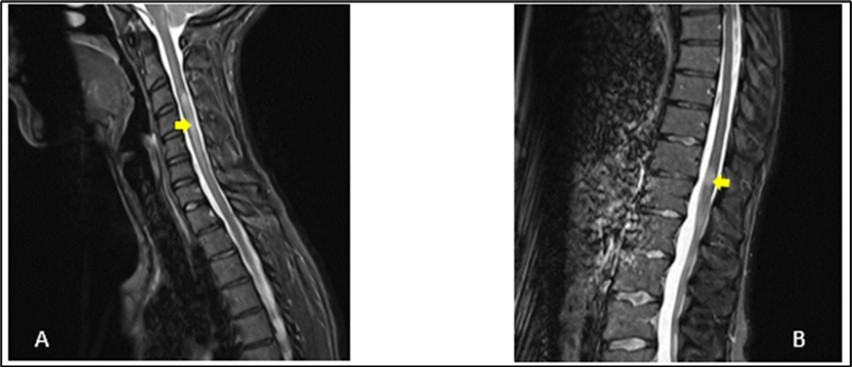

A 27-year-old girl presented at the emergency department, at a hospital in the Paris region on March 9, 2020 with complaints of left interscapular pain, paresthesias and weakness in the ipsilateral upper limb. These symptoms followed paresthesias on the fingertips of her right hand the day before her admission. She did not report fever, sphincter disorder or gait disturbance. No eye symptoms reported. In her medical history, she was treated two weeks earlier for pneumonia with COVID-19. There was no another previous infectious episode apart from the COVID-19. She had no history of diabetes, hypertension, cerebrovascular disease or migraine. She had not history of multiple sclerosis or Neuromyelitis Optica Spectrum Disorder (NMOSD). There was no history of smoking, contraception drugs intake or any prolonged drug intake. On the first examination in the neurology department where she was transferred on the same day of her admission, she had good general condition and was apyretic. She had a pulse rate of 74/min and the blood pressure was at 130/80 mmHg. The neurological evaluation showed on the left side, a muscular weakness grade 4 in the proximal part and grade 3 in the distal part of upper limb, and in the lower limb, the weakness graded at 3 in the distal part, using the Medical Research Council Scale (MRC) for muscle strength. There was no weakness on the right side. Deep tendon reflexes in both left and right were normal. Babinski sign was found on the left side. She presented tactil and algic hypoesthesia in the lower left limb ascending until the C4 level in the left side. There was no perineal sensitive trouble. The remain neurological exam including, higher functions, cranial nerves, was with no particularity. Otherwise, cardiovascular and respiratory systems examination were within normal limits. Blood laboratory tests were within the normal ranges, including complete blood count (CBC), C-Reactive protein, renal and liver functions and blood serum ionogram. Human Immunodeficiency Virus (HIV) tests including p24 antigen and antibodies to HIV were negative. Syphilis serology and Aquaporin 4 antibody were also negative. Encephalic Magnetic Resonance Imaging (MRI) demonstrated scattered hyperintense lesions on FLAIR imaging in deep hemispheric and juxtacortical white matter in supratentorial and in infratentorial floors (Figure 1). Medullary MRI showed T2 hyperintense lesions in left cervical hemi-marrow extending from C3 to C6, at T3, T4, T11 and T12 levels (Figure 2). These lesions were not enhanced after injection of gadolinium. The Cerebrospinal fluid (CSF) appeared to be colorless and clear with no cell detected microscopically; cerebrospinal protein level, 0.4 mg/L, glucose (Glu) level, 3.2 mmol/L; and instant blood glucose level, 5.2 mmol/L. CSF bacterial culture demonstrated no growth after 3 days, and herpes simplex virus 1 and 2, varicella-zoster virus test was negative. Reverse transcription-polymerase chain reaction (RT-PCR) assay test for COVID-19 was negative in the CSF. The final diagnosis was an ADEM secondary to novel coronavirus (nCov) infection. She was given methylprednisolone (1000 mg IV per day for 5 days) followed by Intravenous Immunoglobulin (IVIG) therapy at 0.4 g/kg daily for 5 days. Together with chemotherapy, she received physiotherapy coupled with occupational therapy. The outcome was good with improvement of weakness and paresthesias. There was residual tingling on the fingertips of the left hand. The patient was discharge on day 13.

Figure 2.Sagittal T2-weighted spine MRI showing at cervical level (A), a spontaneous hyperintense lesion of 5 cm from C3 to C6 and at thoracic level (B), a spontaneous hyperintense lesion of 1.5 cm from T11-T12

We have described a case of ADEM post COVID-19 infection in a 27-year-old girl who was taken care of in a hospital in the Paris region. She was treated in the same hospital 2 weeks earlier for an acute respiratory distress syndrome caused by COVID-19 infection. The period of the study was at the beginning of the outbreak of COVID-19 infection in France. COVID-19 is a new entity caused by the severe acute respiratory syndrome coronavirus 2 (SARS CoV-2). It is known to cause respiratory complications, from mild upper respiratory symptoms to acute respiratory failure. ADEM is an immune-mediated inflammatory disorder of the CNS characterized by a widespread demyelination that predominantly involves the white matter of the brain and spinal cord. The condition is usually precipitated by a viral infection or vaccination 7. For this, it is also named post-infectious encephalomyelitis. The infection typically comes before the onset of symptoms of approximately 2 days to 4 weeks 8. This was the case of our patient who presented two weeks before the onset of neurological symptoms, a pulmonary infectious episode for which the etiological research revealed a COVID-19 infection. The pathological abnormalities during ADEM are post-infectious changes of immune origin affecting the central nervous system. These changes are present in the small blood vessels of both white and grey matters. As the lesions become older, the macrophages increase and lymphocytes decrease in number. At a late stage of disease foci of fibrillary fibrosis can also be seen in adjacent brain tissue. Although postinfectious encephalomyelitis typically involves the white matter, lesions in grey matter have also been seen and may involve basal ganglia and the thalamus 3, 4. Due to the impossibility to perform an anatomopathological examination in our patient, MRI of the CNS constitute a reliable tool to translate the diffuse CNS damages of the brain as well as of the marrow. These elements are well presented on the imaging performed by our patient (Figures 1, 2). There is a lack of detection in CSF in most cases besides evident inflammation. This raises the possibility that the majority of ADEMs associated with COVID-19 could be the result of immune-mediated mechanisms or molecular mimicry which generates an aberrant neuro-inflammatory loop, so the virus does not need to cross the blood-brain barrier to cause damage to the CNS 9. As with ADEM occurring after other viral infections, the mechanism would be the same in the case of COVID-19 infection. The presence or history of any other systemic infection, particularly viral, would have made the diagnosis unlikely. As the patient had no other infection apart from COVID-19 in the days preceding the neurological symptoms, it is therefore perfectly legitimate to consider this infectious episode as the trigger for the cascade of immune reactions at the origin of the neurological symptoms. In most cases, ADEM has a monophasic course and is self-limiting, with return to neurological baseline within 3 months after the onset of symptoms. Occasionally, a subset of ADEM patients with relapsing disorders, including recurrent disseminated encephalomyelitis (RDEM), multiphasic disseminated encephalomyelitis (MDEM), neuromyelitis optica spectrum disorders (NMOSD), and multiple sclerosis have been reported 10. The clinical presentation is heterogeneous. Typically, patients show prodromal symptoms such as fever, headache, malaise, nausea, and vomiting. The acute phase occurs with encephalopathy, characterized by altered behavior including irritability, confusion and consciousness like lethargy, stupor, or coma associated with multifocal or focal neurological deficits depending on the area involved in the demyelinating process 11. Other neurological findings have been reported in ADEM related to COVID 19. Laura Zelada-Ríos reported in 2021 pyramidal signs (44.4%), brainstem signs (11.1%), cerebellar signs (22.2%), seizures (33.3%) and peripheral nerve compromise (11.1%) 12. ADEM in COVID 19 pediatric patients have been also reported in children 6, 13. MRI plays a key role in the diagnosis of ADEM and should be performed as soon as it is suspected. The typical findings are identified as lesions with signal hyper-intensity in FLAIR and T2 sequences, they are usually multiple, asymmetric, irregular, poorly defined, and greater than 2 cm. In general, the white matter is affected, although it may involve the deep gray matter, the brainstem, the cerebellum, and the spinal cord 12. MRI is also used to consider differential diagnoses 14 multiple sclerosis (MS), neuromyelitis optica (NMO), and neuromyelitis optica spectrum disorder (NMOSD), which can overlap with ADEM in presentation 15. Among these previous diagnoses, multiple sclerosis remains the most important differential diagnosis of ADEM. Both clinically and paraclinically, these 2 pathologies share almost the same criteria. Thus, Swharz et al, in a cohort of 40 patients, fail to identify any exclusive feature characteristic of either condition. Similarly, cerebrospinal fluid findings are not distinctive enough to allow differentiation between ADEM and multiple sclerosis in a single patient. Even MRI studies were not able to differentiate ADEM from multiple sclerosis. Approximately, 50% of the patients with ADEM had MRI features that were suggestive of multiple sclerosis. however, fever, loss of consciousness, and meningism are infrequently observed but are highly suggestive of ADEM because these symptoms are rare in multiple sclerosis 16. It results from this study of Swharz, that the chronology of the neurological symptoms with a pre-existing systemic infection, viral especially constitutes a very determining profile. These data of the interrogation were at the base of the diagnosis of ADEM post covid of our patient more especially since there were no clinical or paraclinical arguments in favor of another potential differential diagnosis, that is Devic's neuromyelitis optica. Differences exist between encephalitis associated with COVID-19 and ADEM associated with COVID-19, one of them is temporality. Unlike ADEM, neurological symptoms usually appear simultaneously with respiratory symptoms in COVID-19-associated encephalitis. Brain inflammation expressed by pleocytosis is more frequent in encephalitis associated with COVID-19 17. Sharing the same pathophysiological mechanisms as other post-infectious encephalomyelitis, the principles of the treatment of post-COVID ADEM therefore remain similar. The treatment of ADEM is targeted to suppress a presumed aberrant immune response to an infectious agent or a vaccination. Treatment with intravenous corticosteroids (methylprednisolone) or adrenocorticotrophic hormone in large doses has been shown to improve the outcome 18, 19. Corticosteroids are usually associated with plasmapheresis and intravenous immunoglobulin. This association have been shown to produce dramatic improvement in some cases where corticosteroids have failed 16. In some cases, cytotoxic agents have been used with success 18. Functional rehabilitation as a support treatment is a useful contribution even if the publications do not usually mention it. Regarding clinical outcomes, it is generally favorable in the cases of ADEM. This was the case of our patient as well as the results reported by L. Zelada-Ríos et al. 12.